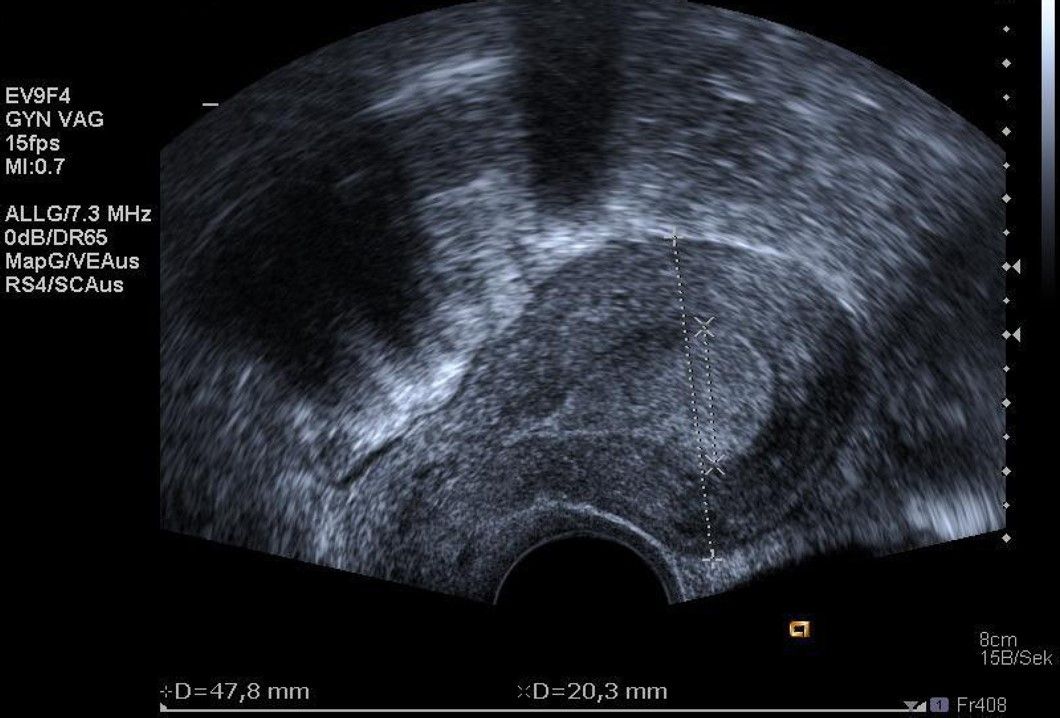

Die Diagnosestellung erfolgt in aller Regel mittels transvaginalem (durch die Scheide) Ultraschall. Nur in Ausnahmefällen ist eine MRT-Untersuchung notwendig.

Abb. 1: Ultraschalldarstellung eines submukösen Myoms (unter der Gebärmutterschleimhaut)

Abb. 2: Ultraschalldarstellung eines intramuralen Myoms (in der Gebärmuttermuskulatur) der Gebärmutterhinterwand